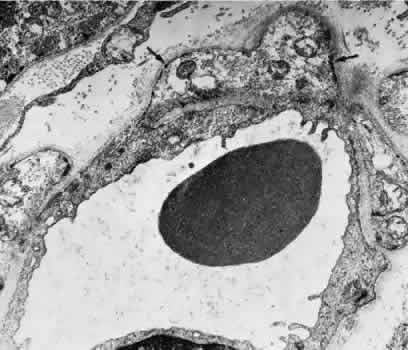

Venules are usually less than 20 μm in diameter.15 The media is composed of a single layer of cells resembling pericytes, containing poorly developed myofilaments and dense bodies. Elastin is not present. The adventitia contains little other than the basement membrane surrounding the pericyte (Fig. 5).

Fig. 5. Electron micrograph of a human retinal venule. E, endothelial cell. The pericyte (P) contains abundant mitochondria and rough-surfaced endoplasmic reticulum. Pinocytotic vesicles are present, and the myofilaments are poorly developed.